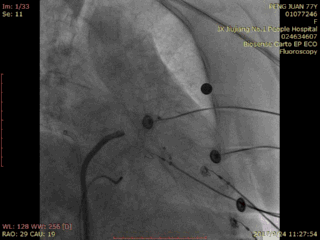

释放后造影:

RAO 30 CRA 20:

RAO 30 CAU 20: